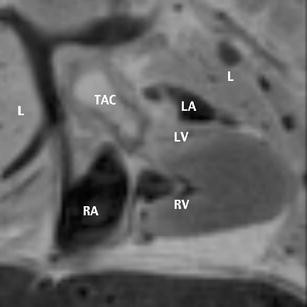

Different techniques are used in fetal cardiology, and their accuracy has been demonstrated on several occasions. Color Doppler US has proved to be a reliable and valuable tool in the diagnosis of fetal cardiac abnormalities. Magnetic resonance imaging (MRI) of the fetal heart has, so far, played no role in prenatal diagnostics. We report on a truncus arteriosus communis diagnosed prenatally during a screening ultrasound at 22 weeks of gestation. In addition to real-time ultrasound and color Doppler echocardiography, fetal MRI was performed. Fetal echocardiography arose suspicion of a type I common trunk. Fetal MR showed solely a widened vessel coursing retrocardially and additionally an inhomogeneous fluid distribution of the lung not shown on prenatal US. After termination of pregnancy at 23 weeks of gestation, MR fetography and autopsy were performed, and both found a type II common trunk. MR autopsy of the heart was very reliable in this case and could be an alternative when fetal pathology is not available for different reasons. Postmortem MRI was also able to demonstrate the inhomogeneous fluid distribution in the lung, which was confirmed by autopsy. Fetal and postmortem MR was reliable in the detection of an inhomogeneous fluid distribution in the lung not shown on prenatal US, providing a relevant additional finding to US. Therefore, MRI should be used more often in fetal cardiology, although it still must be further developed.

Fig. 1

Fig. 2

Fig. 3

Fig. 4

Fig. 5

Fig. 6

Fig. 7

Fig. 8